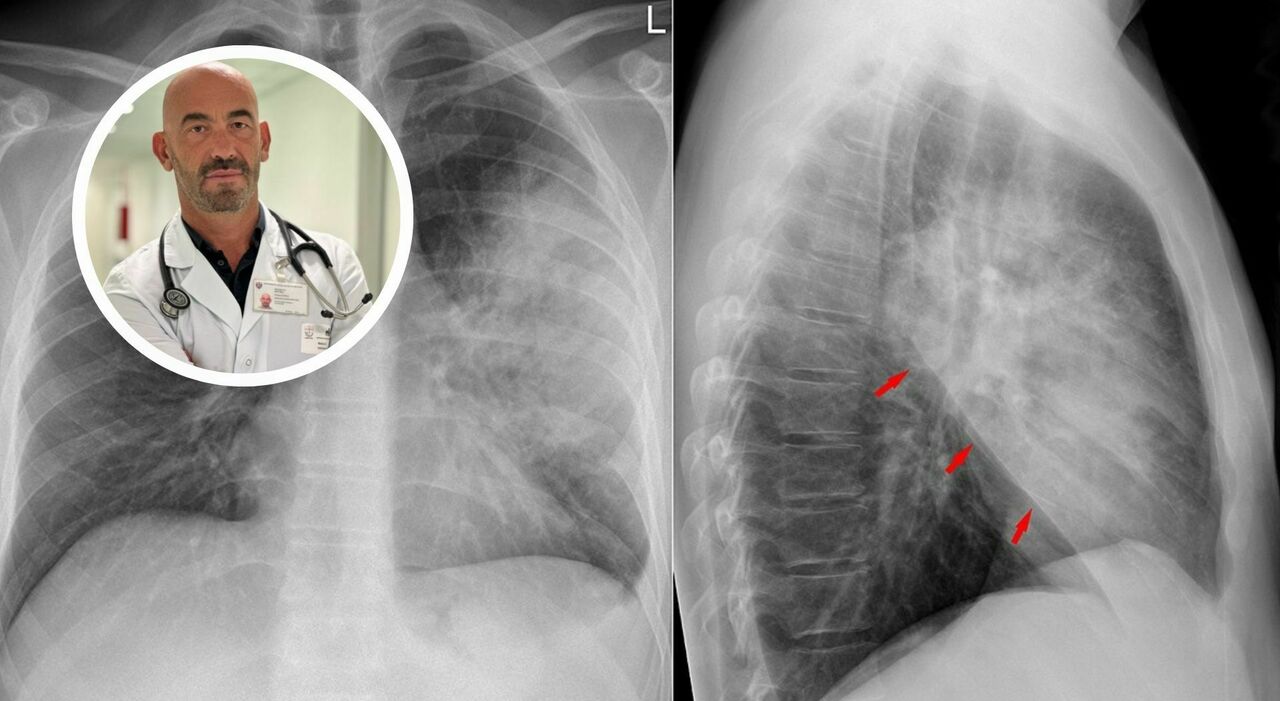

«I nostri ospedali sono già oggi pieni di casi di polmonite», avverte Matteo Bassetti, direttore Malattie infettive dell’ospedale policlinico San Martino di Genova. Ogni anno in Italia ci sono almeno 150mila ricoveri e 9mila i decessi. Ma i dati «importanti» dell’andamento dell’influenza (e altri virus) in Australia non fa ben sperare per quest’anno. Anche perché alcuni recenti casi noti, come per la morte del maestro Peppe Vessicchio (per la forma interstiziale) o per il ricovero dell’allenatore del Bologna Vincenzo Italiano, hanno riportato alta l’attenzione. Anche se, fortunatamente, in Italia la mortalità è una delle più basse d’Europa. Vediamo insieme cause, sintomi e come riconoscere la polmonite con il dottor Bassetti.